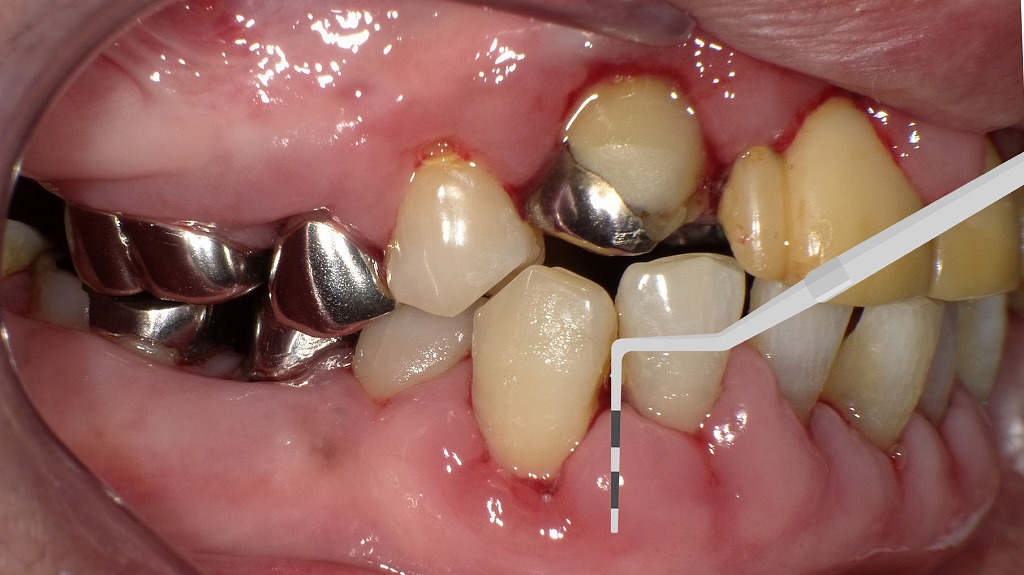

プロービングで分かる歯周病の進行度:重度と健康な歯の明確な違い

〈解説-深い歯周ポケットが確認できる重度歯周病の状態〉

プローブを挿入すると、根の深い位置までスッと入ってしまい、明らかに深い歯周ポケットが形成されています。

X線上でも、歯根周囲の骨が大きく吸収されており、水平的・垂直的な骨欠損が認められます。

これは歯周病が進行し、歯を支える骨が減っている典型的な所見です。

ポケットが深いほど細菌が停滞しやすく、動揺・腫れ・出血・口臭などのリスクが高まります。